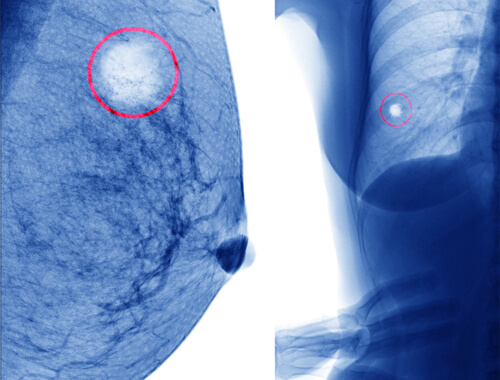

Una ciste al seno è una raccolta di liquido all’interno della mammella, cioè, una sorta di “borsa” ben definita di dimensioni normalmente piccole, che di solito contiene liquidi.

Quando nei controlli al seno di routine si riscontra un qualche tipo di cisti, è consigliabile consultare il medico per effettuare una valutazione della stessa tramite una semplice tecnica.

Se è liquida o semisolida, senza altri segnali che indichino qualche aspetto negativo, come ad esempio del sangue, è nel 98% dei casi una cisti semplice.

Queste non si trasformano in cancro maligno e non sono pericolose.